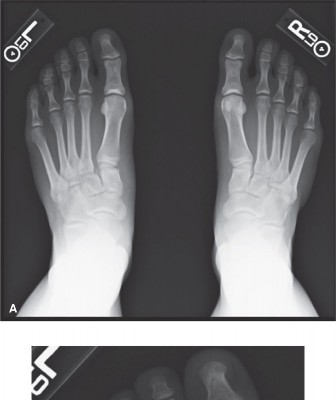

- Standard Views: AP, lateral, and 30-degree oblique views of the foot. Look for loss of alignment, incongruity, and avulsion fractures.

- Weight-bearing (WB) Views: Essential for dynamic assessment. Diastasis between the medial cuneiform and second metatarsal base > 2mm is a definitive sign of instability.

- Stress Views: If initial WB films are equivocal but suspicion remains high, manual stress views (e.g., pronation-abduction stress) under fluoroscopy with local anesthetic can reveal occult instability.

- Comment: This image could represent a pre-operative radiograph (e.g., an AP weight-bearing view) demonstrating subtle widening between the medial cuneiform and second metatarsal base, underscoring the diagnostic challenge and the importance of thorough interpretation.